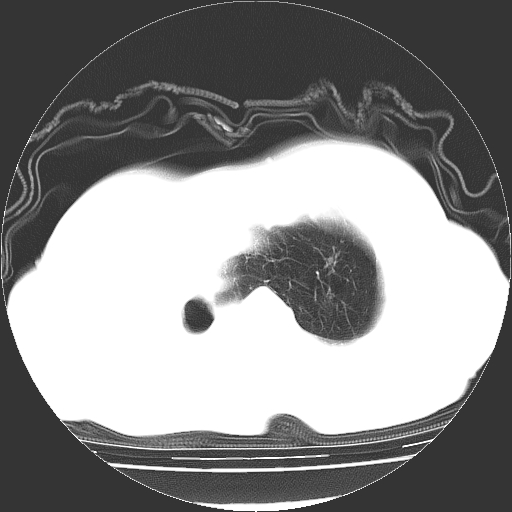

标题: CT23991:女,72岁,咳嗽、憋气一周。 [打印本页]

女,72岁,咳嗽、憋气一周,十年前曾患肺结核及胸膜结核。

右侧毁损肺,右侧纵隔疝

右侧毁损肺,右侧纵隔疝,左肺代偿!

1.右侧损毁肺伴胸膜钙化,2.左肺小结节灶,良性可能大,注意复查。3.肝脏左叶囊肿。4.先天性一侧肺不发育待出外(右侧胸廓无明显塌陷)。对比原片应该非常有帮助。